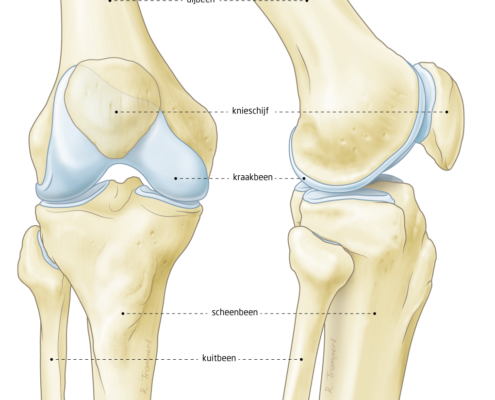

Met knietesten wordt een goede inschatting gemaakt of er sprake is van een probleem aan de buitenkant van je knie zoals de banden, spieren of pezen of dat het probleem meer van bínnen je knie komt, zoals het kraakbeen, meniscus, kruisband etc.

Met name de stabiliteit van de knie is belangrijk. Kruisbandletsel, meniscusproblematiek of artrose kan allemaal de stabiliteit van het gewricht beïnvloeden. In de behandeling is het belangrijk hiermee rekening te houden.

Echografie van de knie speelt een belangrijke rol bij het beoordelen van vocht, cystes, soms losse stukjes kraakbeen, schade of verdikkingen van pezen of banden.